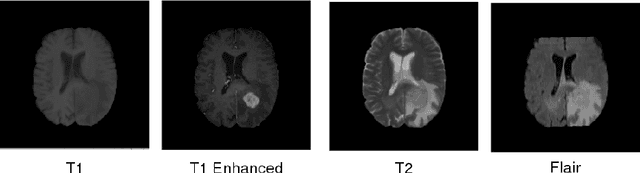

Abstract:In this work, we propose a multi-modal Convolutional Neural Network (CNN) approach for brain tumor segmentation. We investigate how to combine different modalities efficiently in the CNN framework.We adapt various fusion methods, which are previously employed on video recognition problem, to the brain tumor segmentation problem,and we investigate their efficiency in terms of memory and performance.Our experiments, which are performed on BRATS dataset, lead us to the conclusion that learning separate representations for each modality and combining them for brain tumor segmentation could increase the performance of CNN systems.